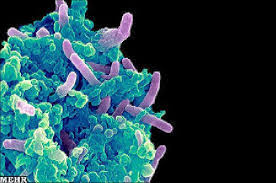

قیمت: 49٬000 تومان - دسته بندی فایل: تحقیقپاورپوینت مایکوباکتریوم توبرکلوزیس (ppt) 37 اسلاید

فروش ویژه پاورپوینت حرفه ای مایکوباکتریوم توبرکلوزیس / تعداد اسلاید : 37 اسلاید

قیمت: 48٬000 تومان - دسته بندی فایل: تحقیقپاورپوینت میکروبیولوژی (ppt) 19 اسلاید

فروش ویژه پاورپوینت حرفه ای میکروبیولوژی / تعداد اسلاید: 19 اسلاید